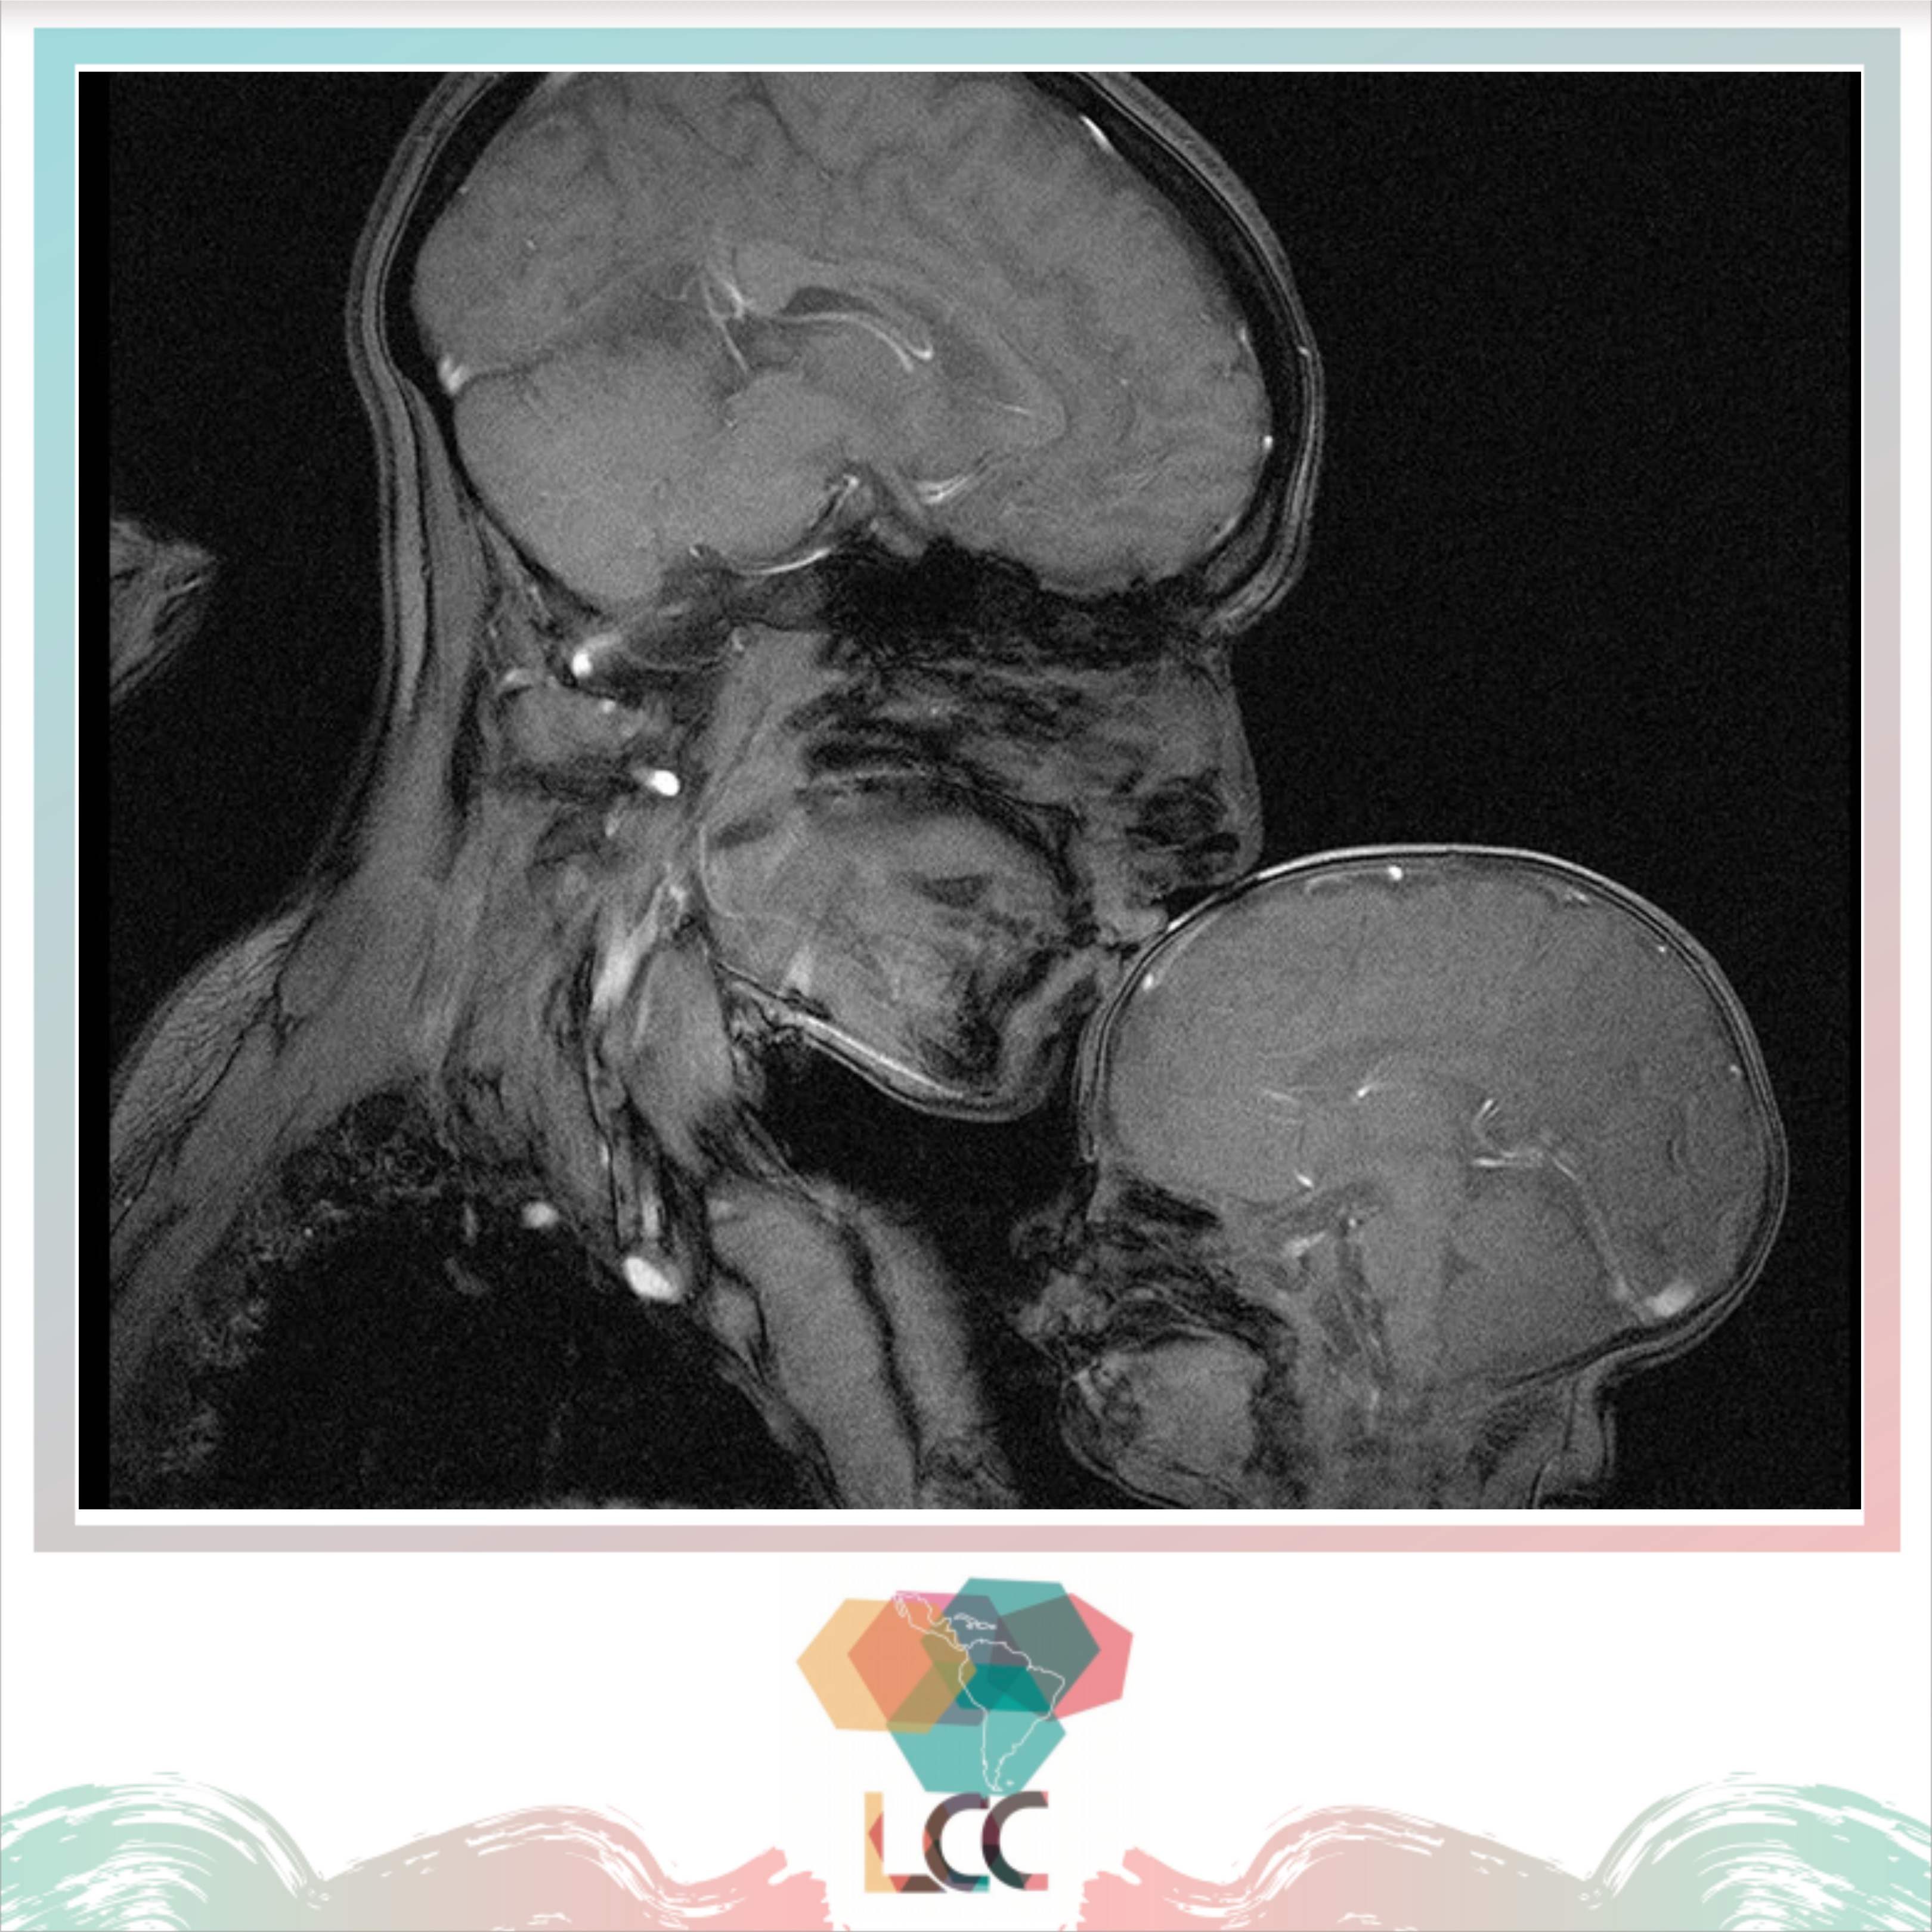

Sobre la resonancia magnética y el amor humano

La resonancia magnética es el resultado del uso de bobinas que, al ser atravesadas por una corriente eléctrica, son capaces de generar un campo magnético a su alrededor y obtener imágenes de casi todas las partes del cuerpo humano. Y también muestras de cariño.